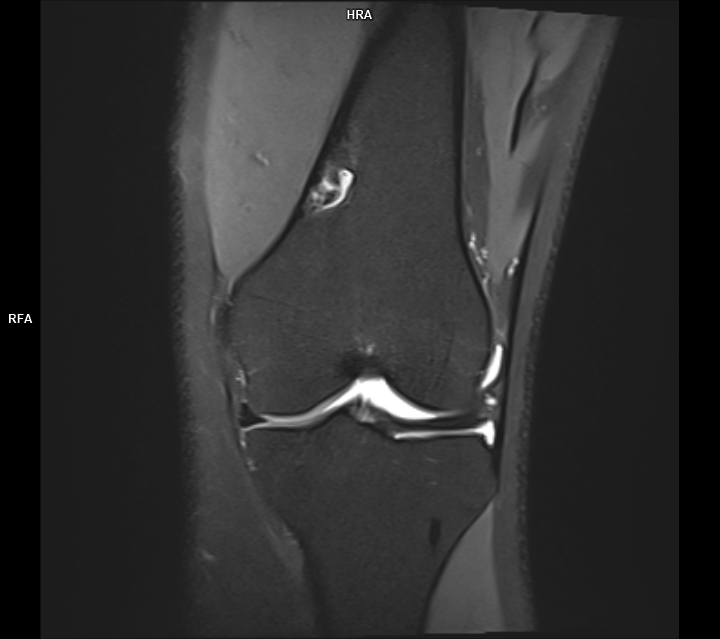

Figura 5, 6: achiziție PD FS coronal